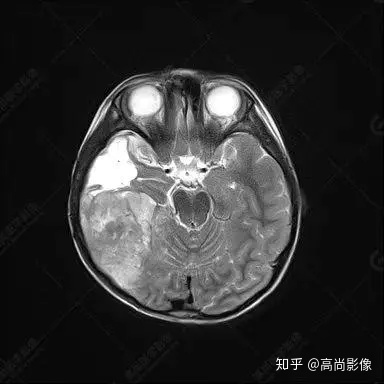

右側(cè)顳葉腫瘤切除術(shù)后(具體不詳):右側(cè)顳部骨質(zhì)不連續(xù)呈術(shù)后改變,右側(cè)顳葉術(shù)區(qū)見片狀長T1長T2信號影,F(xiàn)LAIR呈低信號;術(shù)區(qū)后方右側(cè)顳枕葉見一巨大占位性病變影,邊界欠清,大小約6.2×5.8×4.3cm(前后×左右×上下),信號不均勻,T1WI呈等稍低信號間雜少許高信號,T2WI呈高稍低混雜信號,DWI示部分病灶彌散受限,相應(yīng)ADC圖減低,磁敏感序列見部分呈極低信號,增強(qiáng)掃描可見明顯不均勻強(qiáng)化,鄰近硬腦膜及小腦幕增厚并明顯強(qiáng)化;另延髓右前方及右側(cè)橋小腦角區(qū)見一不規(guī)則形異常信號影,大小約3.2×1.3×3.7cm(左右×前后×上下),呈長T1稍長T2信號,F(xiàn)LAIR呈等信號,DWI未見受限,增強(qiáng)后明顯均勻強(qiáng)化,鄰近腦膜明顯強(qiáng)化。鄰近腦實質(zhì)及右側(cè)顳角明顯受壓;左側(cè)大腦半球未見局灶性信號異常,中線結(jié)構(gòu)稍左移。